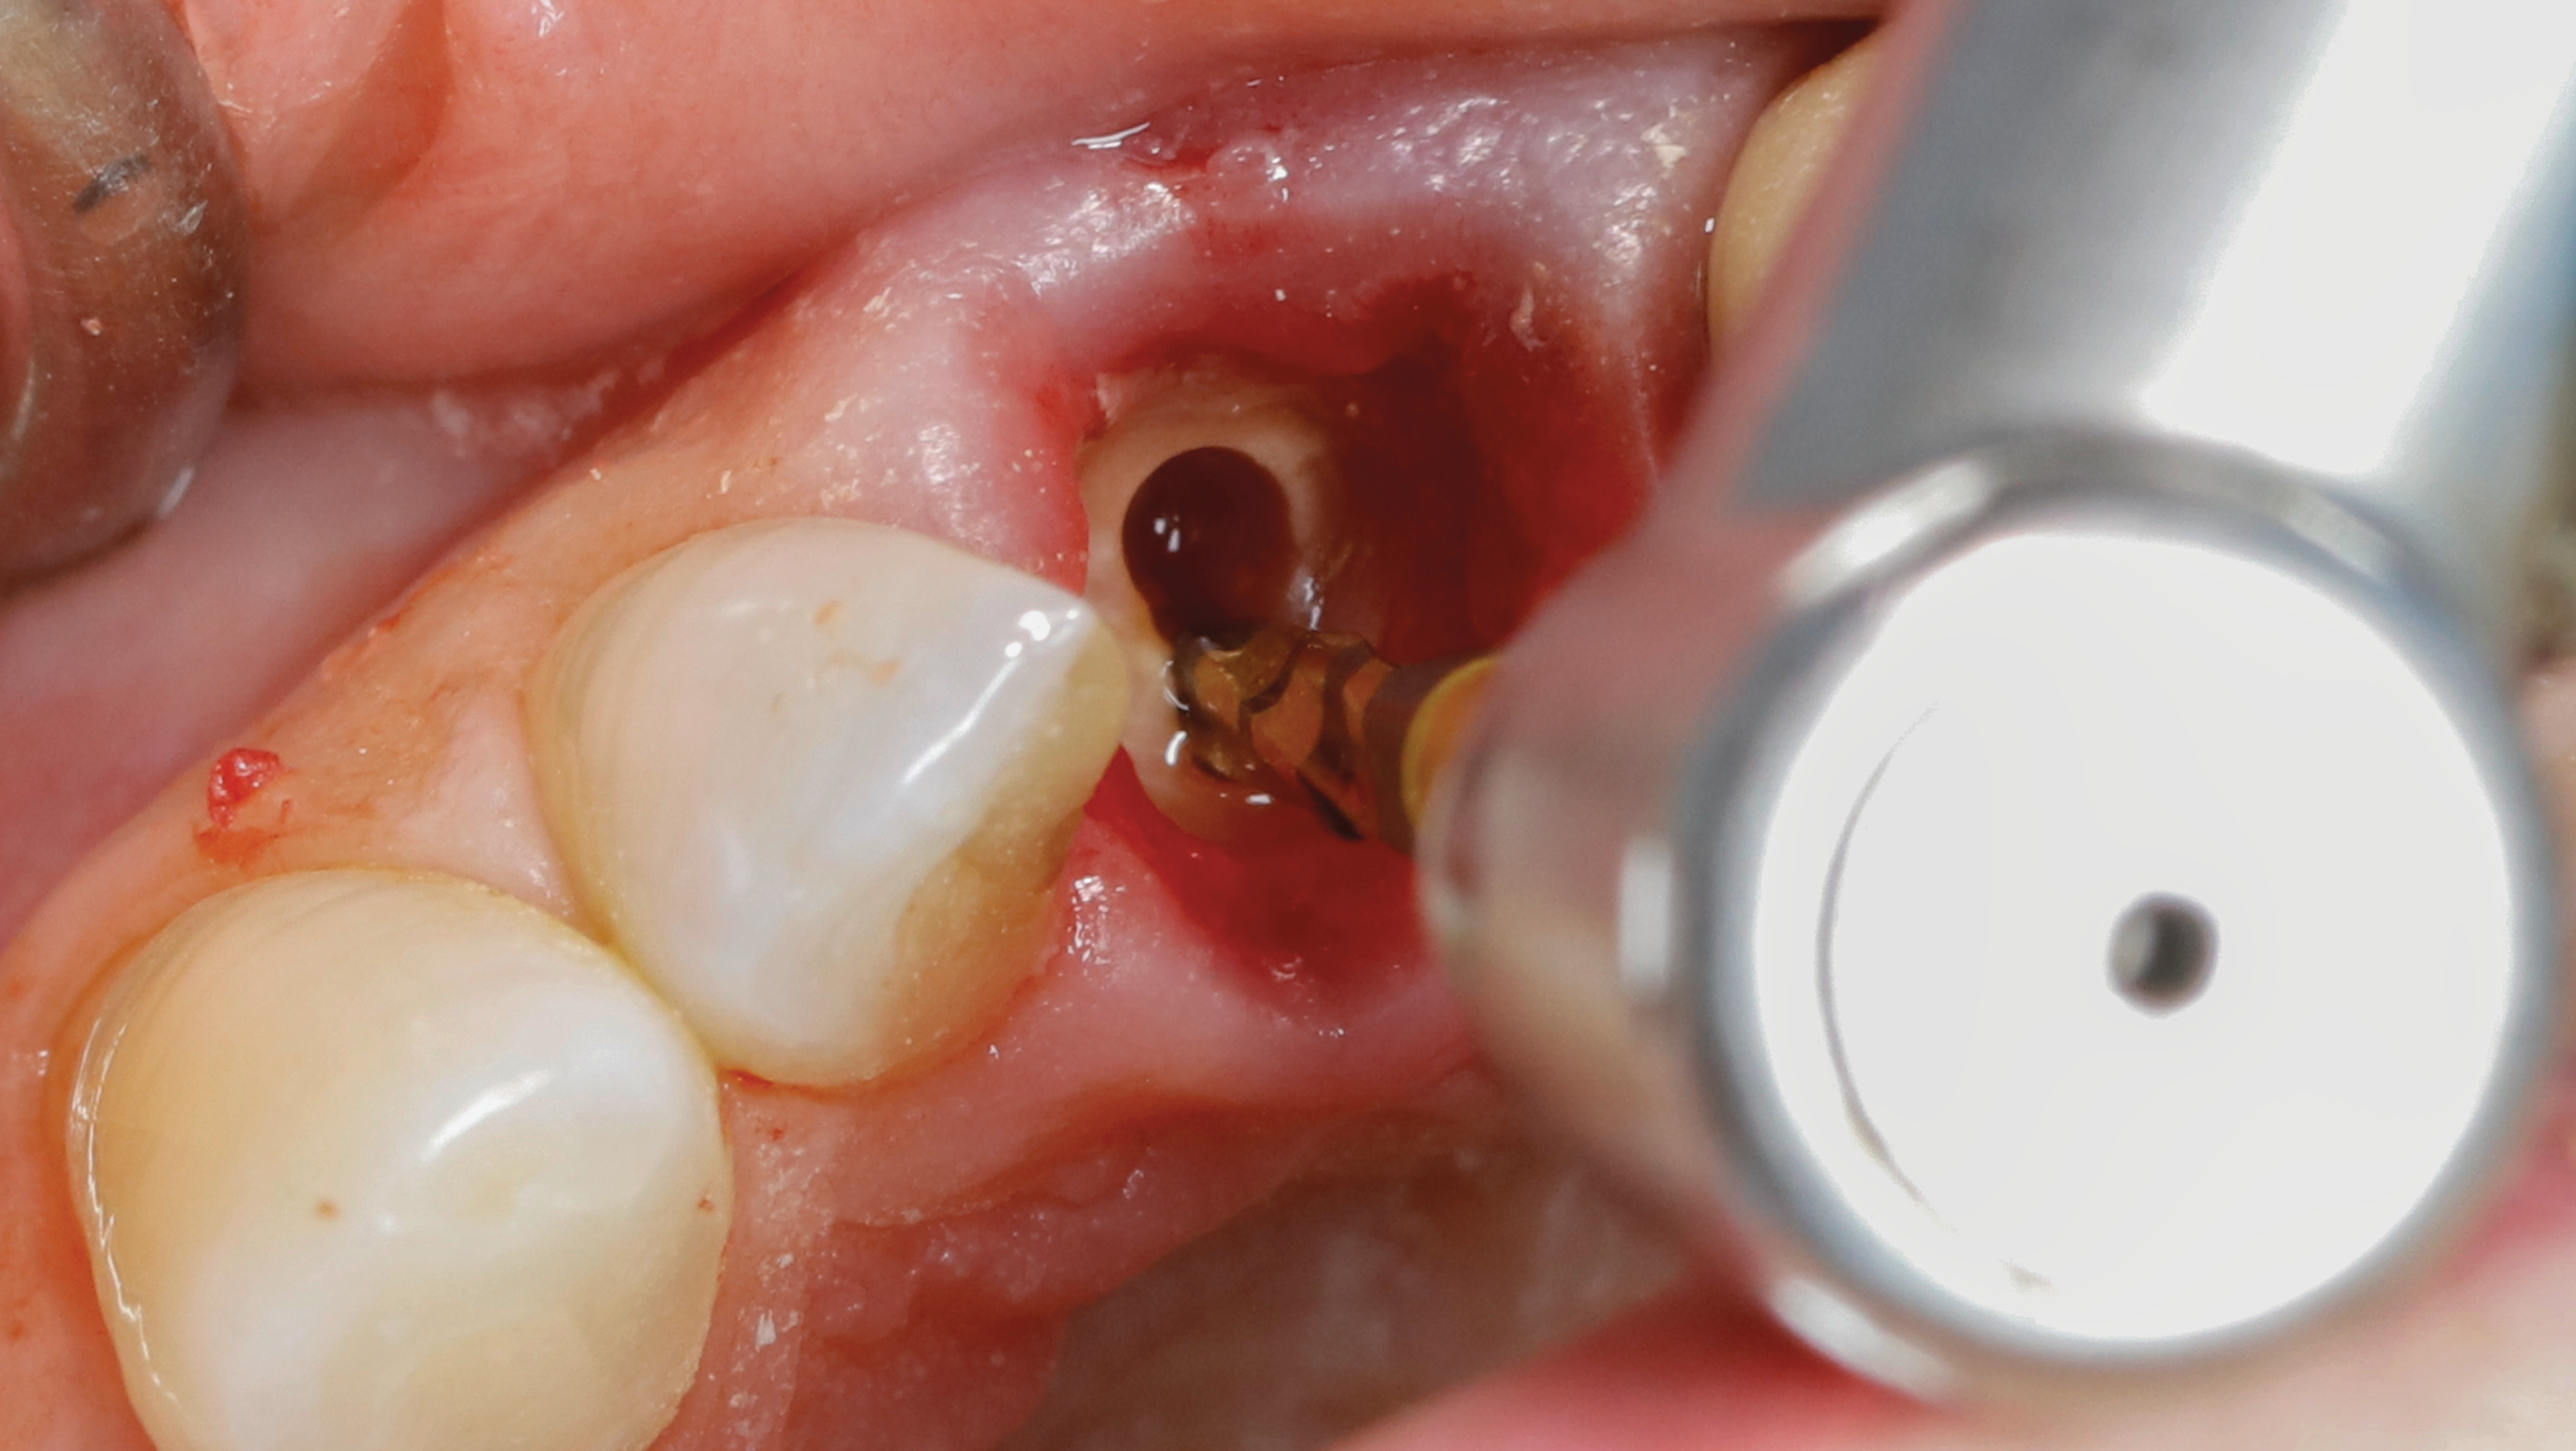

Fig 9. SPOT Step 4: Densah burs VT1525 (2.0) and VT1828 (2.3) are used at 1,200 rpm with irrigation in CW mode to widen the root canal hole trajectory to provide further and complete apex removal. The same burs are then used to establish the implant osteotomy. In some cases, the two trajectory holes might eventually overlap. (Figure 11 is a composite illustration provided by the authors.)

Figure 9

Fig 10. SPOT Step 4: Densah burs VT1525 (2.0) and VT1828 (2.3) are used at 1,200 rpm with irrigation in CW mode to widen the root canal hole trajectory to provide further and complete apex removal. The same burs are then used to establish the implant osteotomy. In some cases, the two trajectory holes might eventually overlap. (Figure 11 is a composite illustration provided by the authors.)

Figure 10

Step 4 - Widen both pilot hole trajectories: Densah® burs VT1525 (2.0) and VT1828 (2.3) are used sequentially in clockwise (CW) mode to widen the root canal hole trajectory to complete apex removal. The Densah burs are advanced in the root canal hole 1 mm beyond the apex. The same burs subsequently are used to establish the preliminary implant osteotomy. In some cases, if the two trajectory preparations overlap it may be necessary to extend the implant site osteotomy 2 mm to 3 mm beyond the apex (Figure 9 through Figure 11).